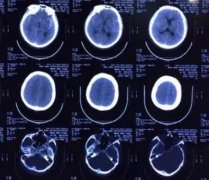

7. 宝宝可以脑部ct吗?宝宝做CT危害介绍

宝宝可以脑部ct吗?宝宝做CT危害介绍

现如今,很多毛病都需要做ct检查,因为很多疾病是外在看不出来的,只有做ct检查才能看的出来。对于9个月宝宝来说,做ct后悔的原因很多,可能对大脑细胞、骨骼、内脏有伤害。宝宝大脑正